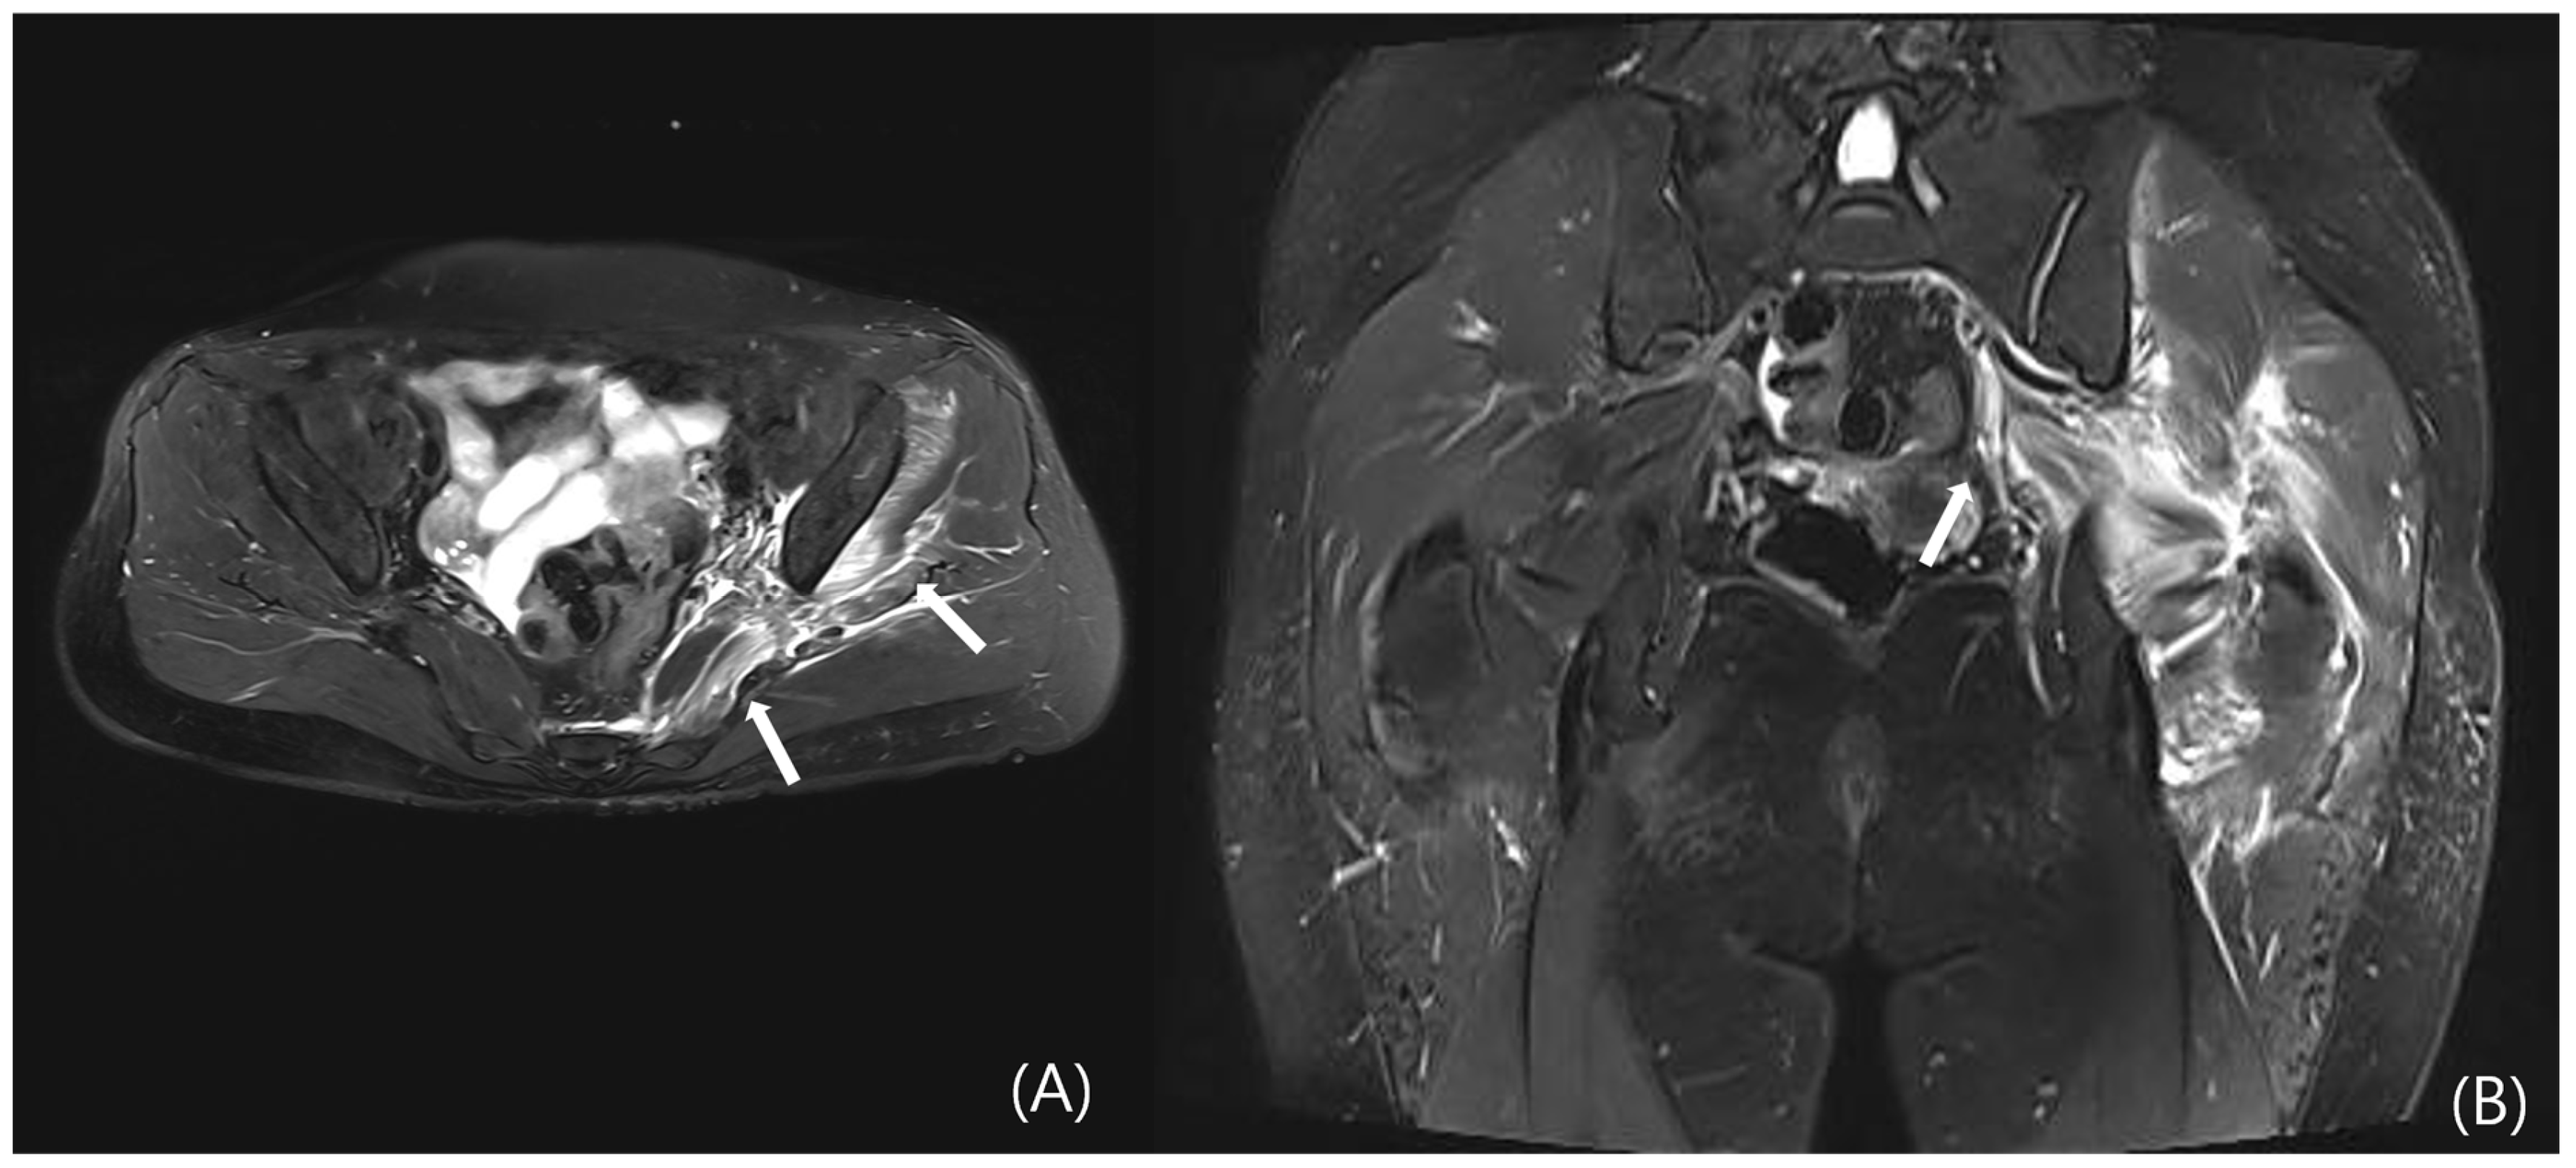

4.3.3. MRI